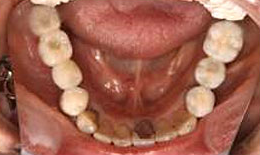

インプラント症例(2) 61歳 女性

治療方法

- 下顎

- インプラントを5本埋め込み、セラミックスクラウンを被せた